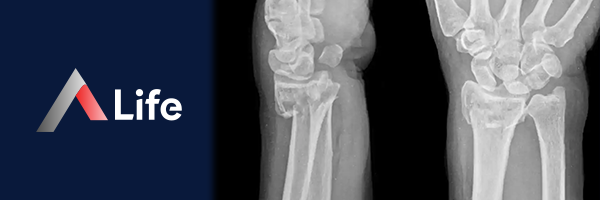

Radius Kırığı

Radius kırıkları, bu kemiğin herhangi bir yerinde meydana gelebilen kırıklardır ve genellikle düşme, spor yaralanmaları veya trafik kazaları gibi travmalar sonucu oluşur.

Radius kırıkları, kırığın yerine göre farklı tiplerde olabilir:

• Distal Radius Kırığı: El bileğine yakın olan radius kemiğinin kırılmasıdır. Bu, en sık görülen radius kırığı türüdür ve genellikle avuç içi üzerine düşme sonucu oluşur. Yaşlılarda ve osteoporoz hastalarında daha sık görülür.

• Radius Başı Kırığı: Dirsek eklemine yakın olan radius başının kırılmasıdır. Genellikle düşme veya doğrudan darbe sonucu oluşur.

• Radius Şaft Kırığı: Radius kemiğinin orta kısmının kırılmasıdır. Daha az yaygın bir kırık türüdür ve genellikle yüksek enerjili travmalar sonucu oluşur.

Distal Radius Kırığı

Distal radius kırığı, el bileğine yakın olan radius kemiğinin (ön kol kemiği) kırılmasıdır. Bu kırık, el bileği kırığı veya Colles kırığı olarak da bilinir ve genellikle avuç içi üzerine düşme sonucu oluşur. Yaşlılarda ve osteoporoz hastalarında daha sık görülür.